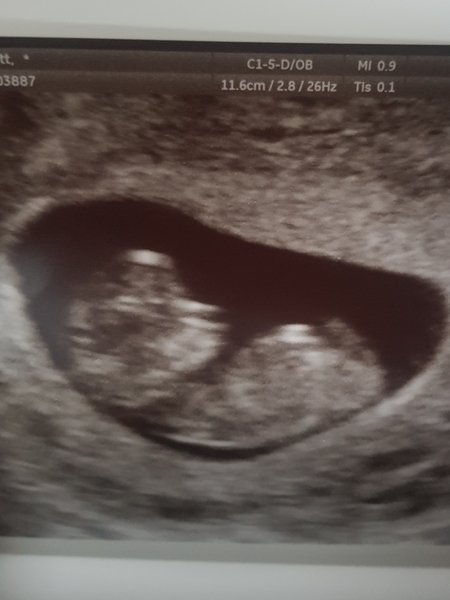

Hi guys checking in I'm 10w2 and got another scan done because from I found out I was pregnant I have developed severe anxiety and not sleeping at nights over worrying 😔 so this has really reassured me! Seen baby's legs and arms moving like crazy and waving at us!

@kileah your scan pic is amazing!! Looks like a proper baby!! Can’t believe it changes so quickly from being a blob just 2-3 weeks earlier.

@Cobblestones I know isn't it crazy the difference 2.5 weeks can make!! Just looking at the early scan pictures now and it didn't look like anything just a blob!!

I'll post pictures of 1st & 2nd scan, 1st scan 7w 6d and 2nd scan 10w 2D

August 2019 Part 3: nausea, scans and big reveals